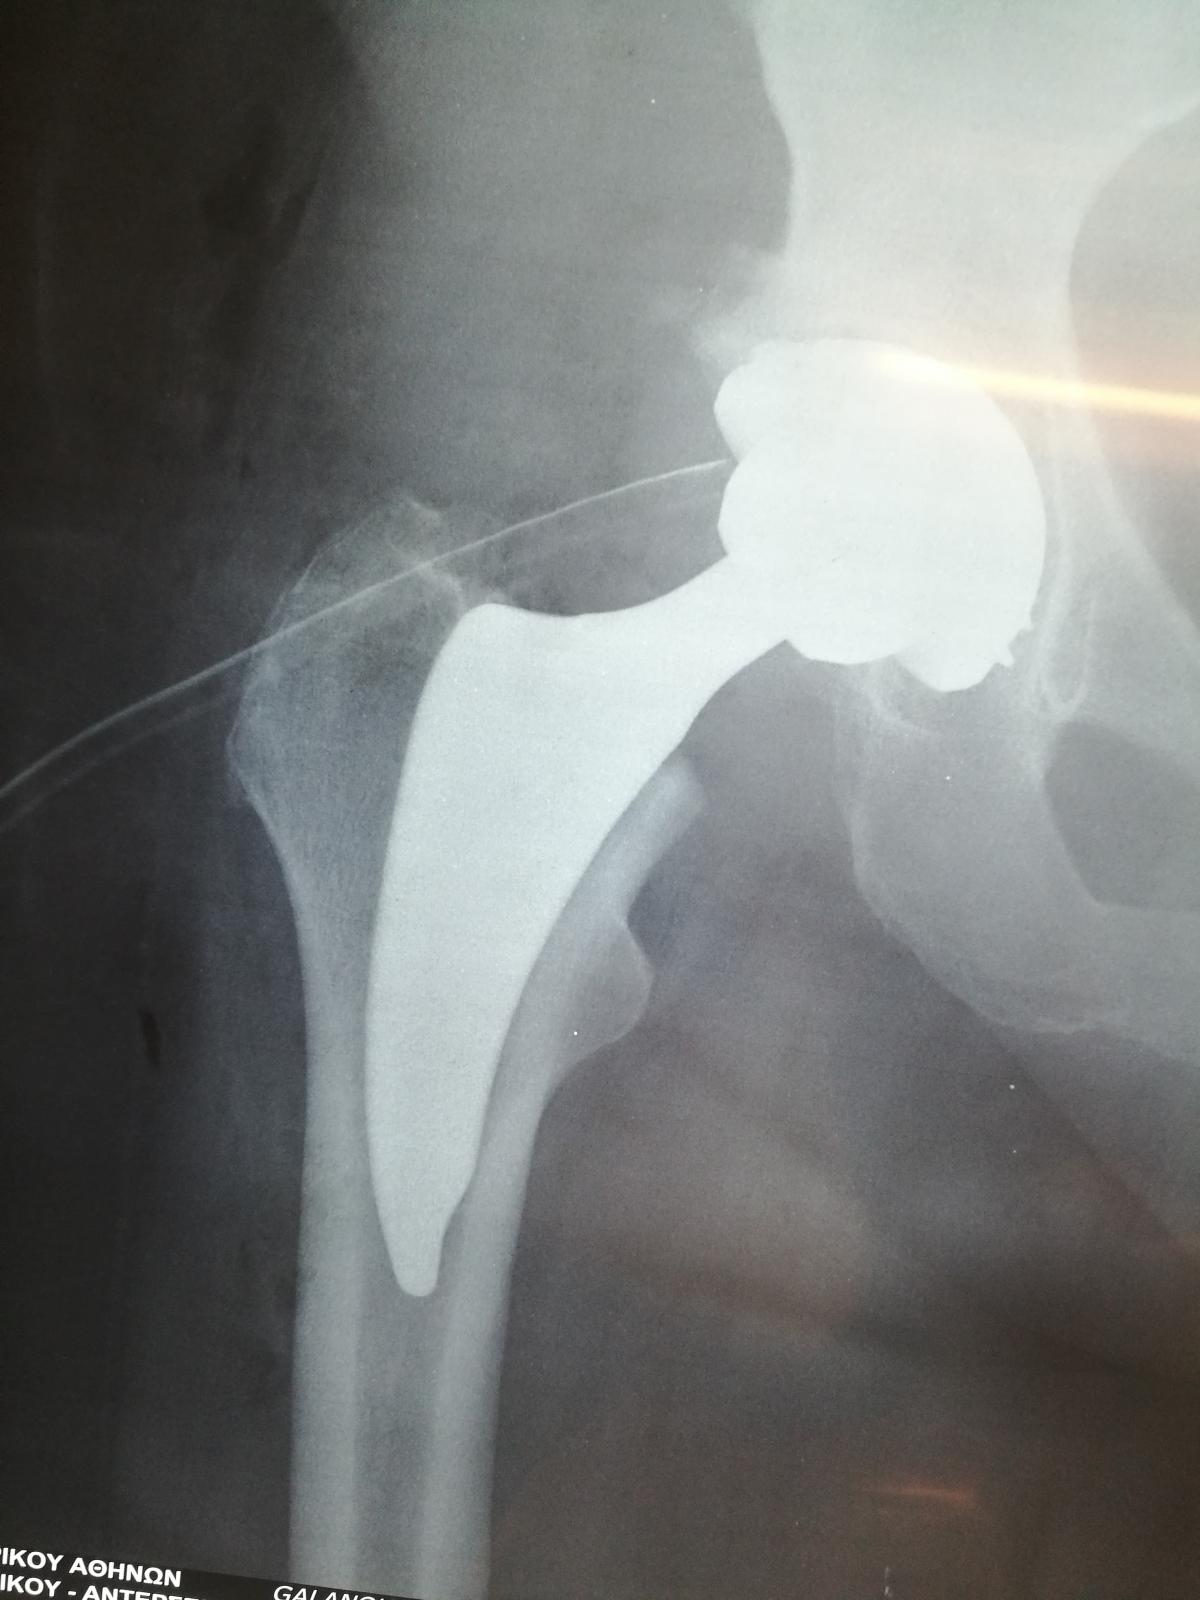

Компанія Lima надала стажування в ортопедичній приватній клініці місті Афіни Греція в листопаді 2019 року. Ендопротезування кульшового суглоба протезами компанії Lima малоінвазивним передньо-латеральний доступом у професора Христодулоса.